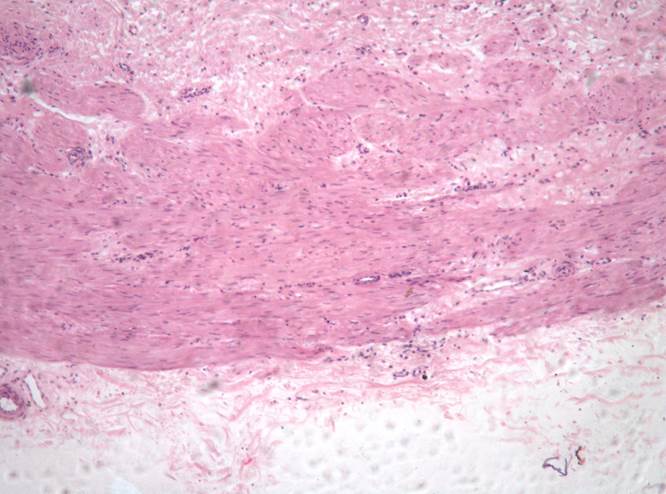

Препарат № 2. «Мочеточник», (окраска гематоксилином и эозином).

Слизистая оболочка:

1. переходный эпителий;

2. собственная пластинка.

II. Подслизистая оболочка.

III. Мышечная оболочка:

3. внутренний слой – продольный;

4. наружный слой – циркулярный.

IY. Адвентициальная оболочка.

5. рыхлая соединительная ткань

6. кровеносные сосуды